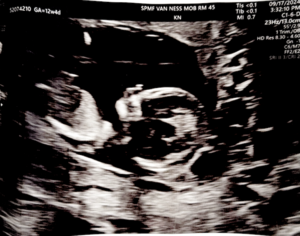

First Trimester Anatomy Scan w/ Nuchal Translucency

[edit]This is an early ultrasound scan that tells you:

- gestational age is as expected

- foetal anatomy is normal

- nuchal translucency is small

The Nuchal Translucency was new to me. It's a test that tells you if your foetus is at risk for Down's syndrome. While our whole genome was sequenced and we knew this was already unlikely, it is possible that the blastocyst has different cells.